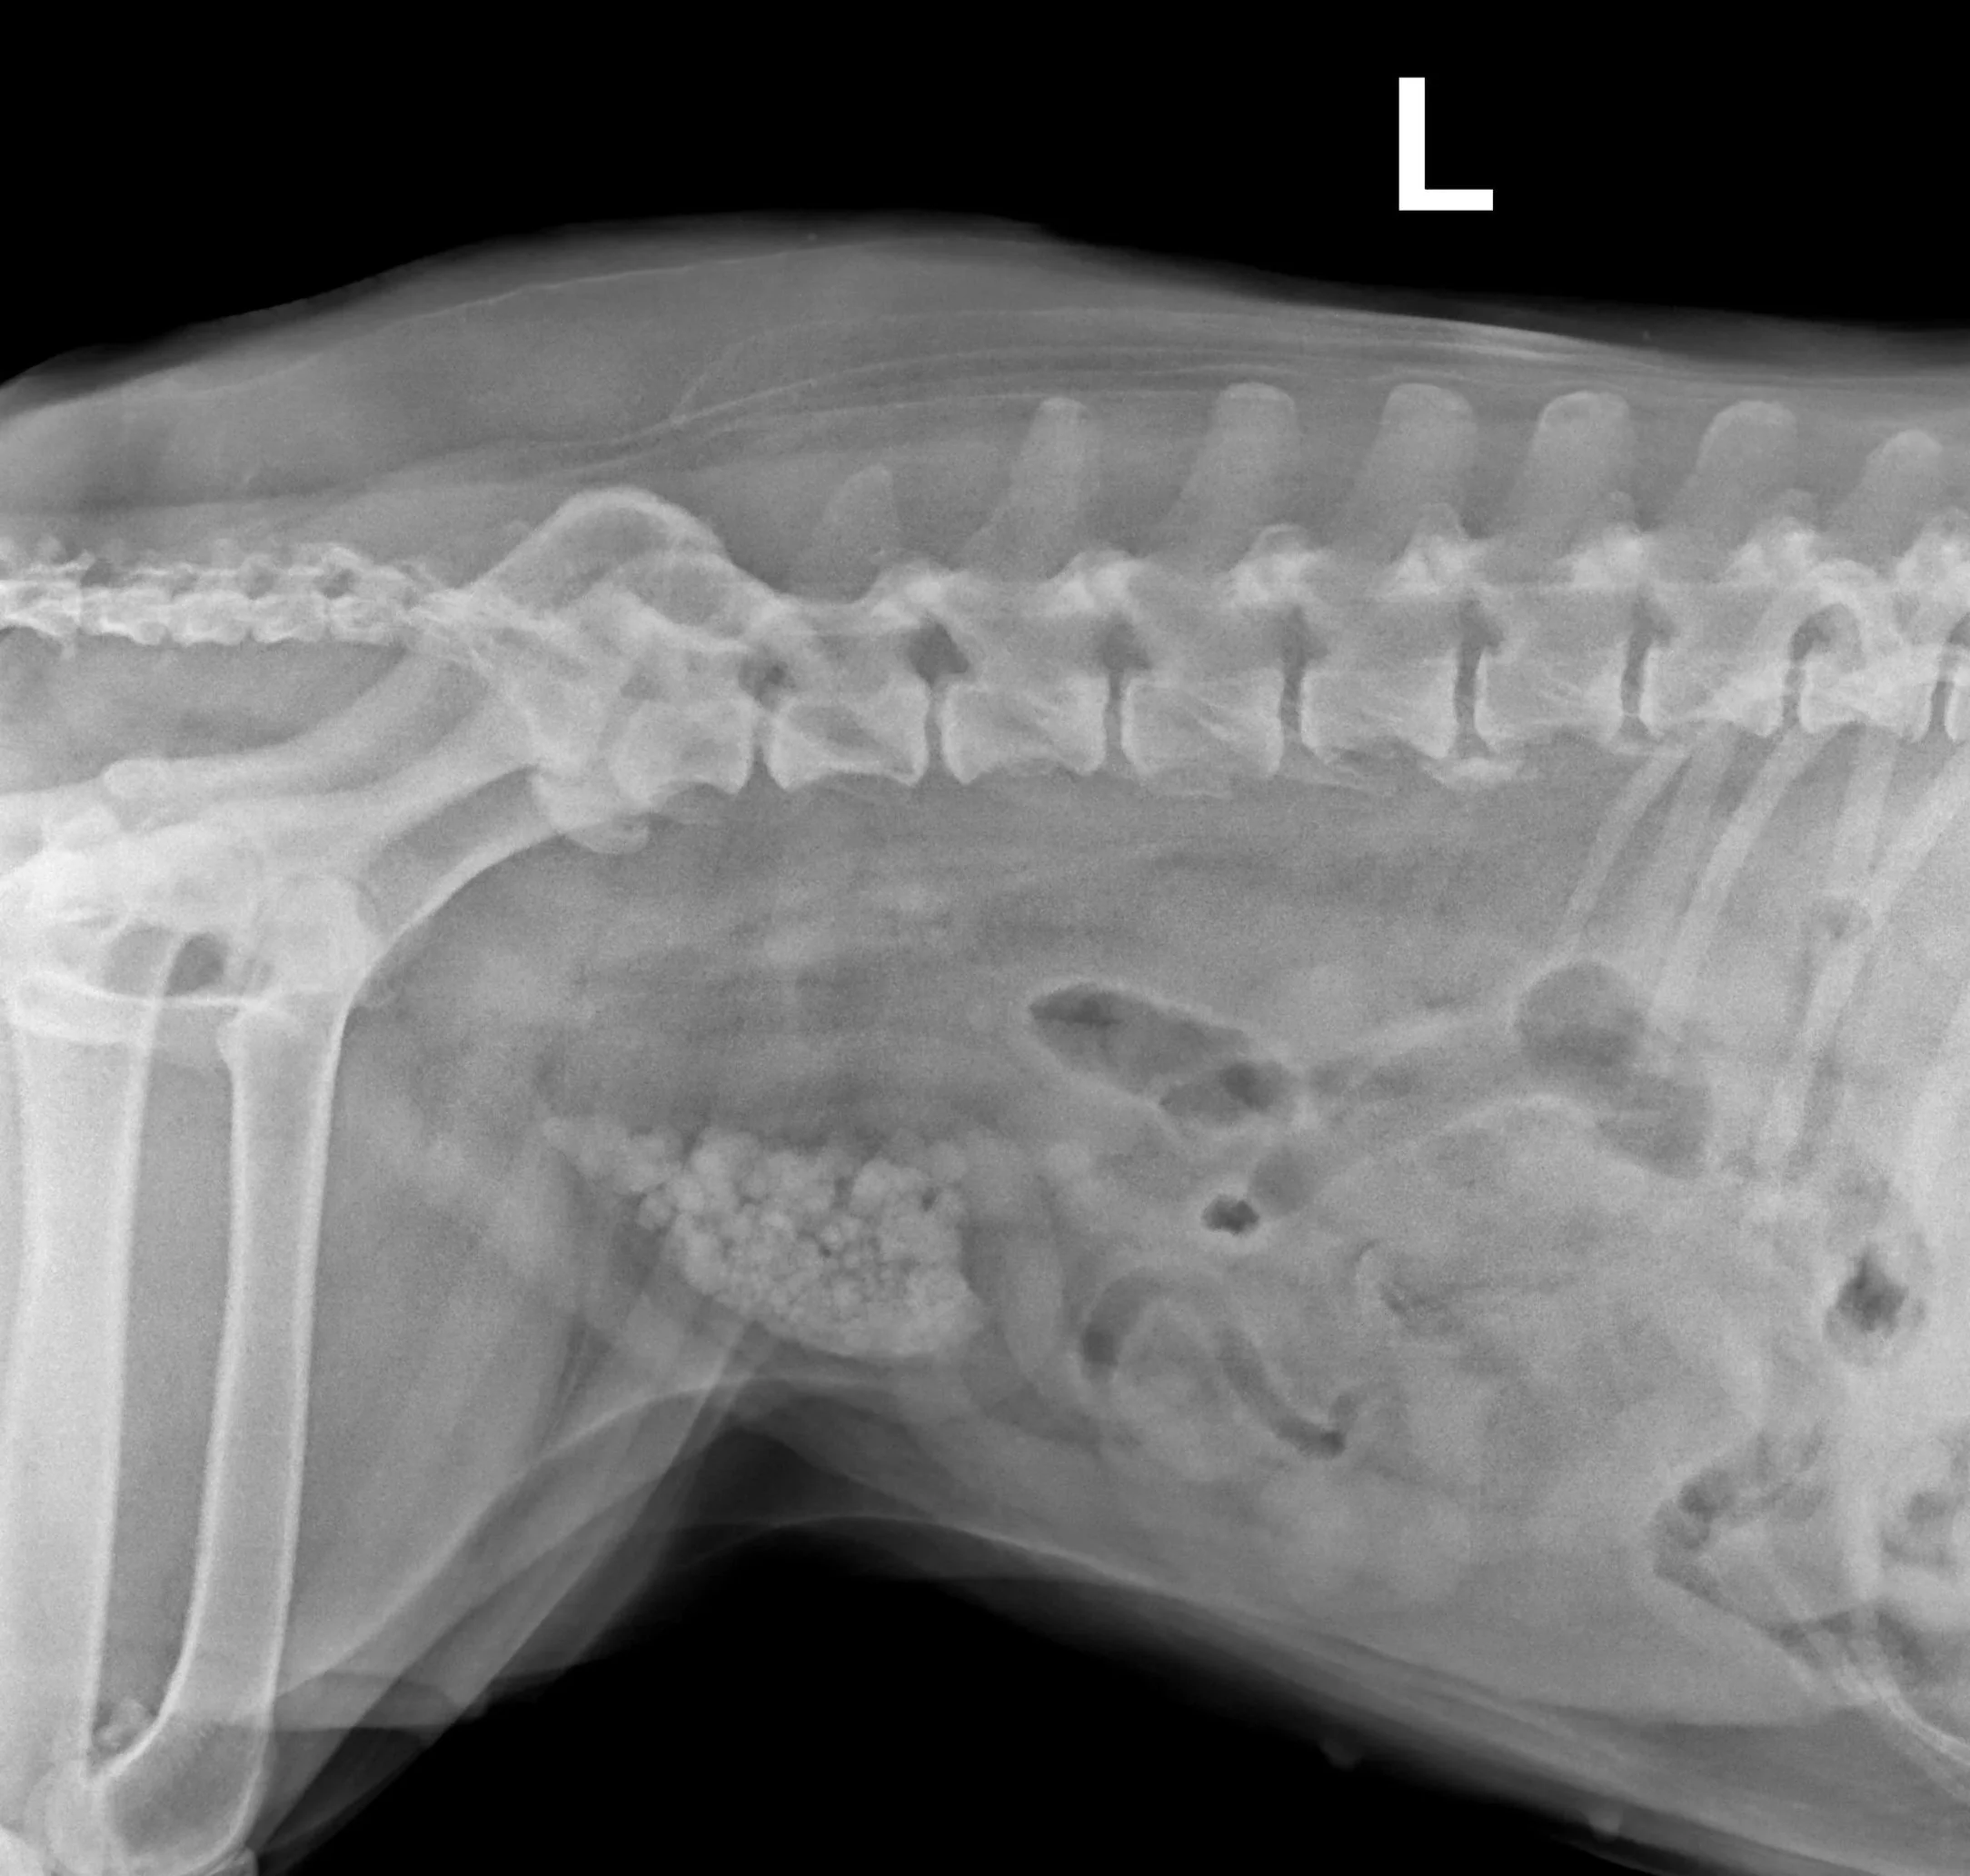

Blasensteine bei einer Hündin, welche wir erfolgreich nach einem operativem Eingriff entfernen konnten.